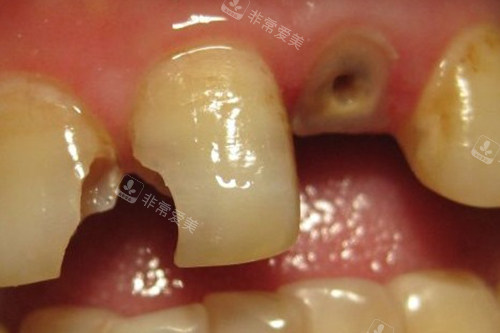

牙齿龋坏到牙根

牙齿龋坏钻洞实拍